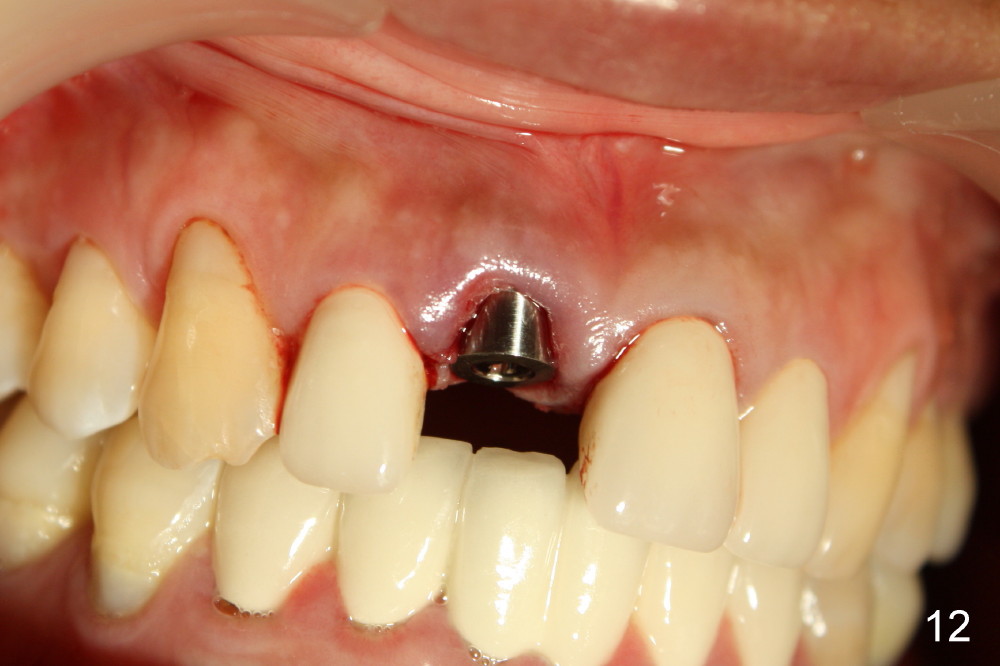

当我们拔出3.5毫米钻头(图五:最后一个钻头)时,就可以看见在舌侧骨板植牙洞型制备(图十一:圆圈)。图十二,图十三分别显示立刻植牙正面观和切缘观,植牙几乎占据所有牙槽窝空间,不需植骨或者缝线。植牙好像没有侵犯邻牙牙根(图十四,图十五,包括七号牙:侧切牙),其实只要熟悉局部解剖(图六至图十),即刻植牙反而容易进行。图十五虚线代表切牙孔,挺接近植牙(I),术后渗血较多,可能与此有关。除此之外,术后病人恢复很快。